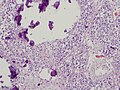

Pineal gland

- Cells in lobulated clusters or linear arrays (low power).

- Pinealocyte:

- Light staining and round nuclei with neuroendocrine look (i.e. salt-and-pepper chromatin).

- Broad rim of light cytoplasm.

- Astrocytes:

- Cylindrical hyperchromatic nucleus ~ 1/2 the size of pinealocyte.

Notes:

- Highly cellular structure - may be confused with (metastatic) small cell carcinoma.

- Often calcified.

- Pineal gland - very high mag.jpg

Pineal gland - very high mag. (WC/Nephron)

- Pineal gland - intermed mag.jpg

Pineal gland - intermed. mag. (WC/Nephron)